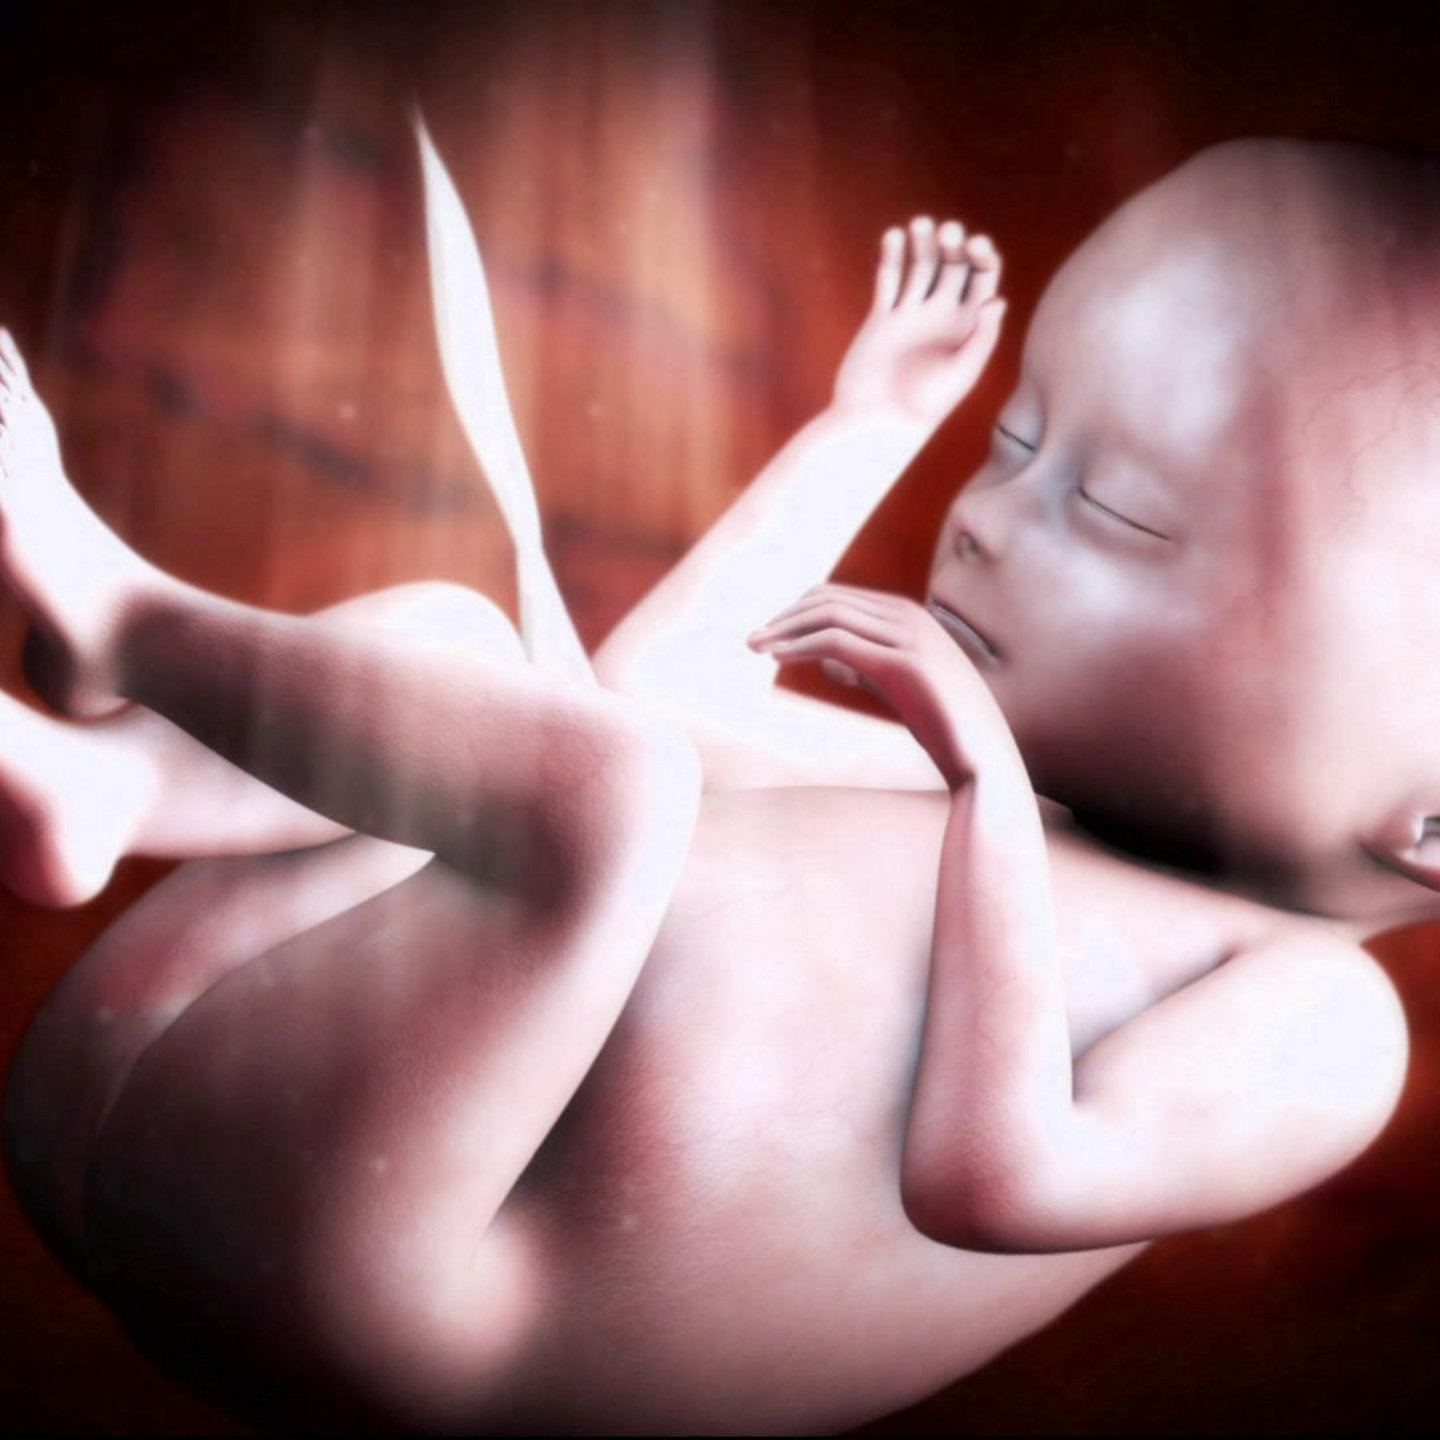

Wie finden sich Spermium und Eizelle? Wann werden im Embryo welche Organe angelegt? Wie verändert sich der Fötus im Verlauf der neunmonatigen Schwangerschaft? Dieser Film porträtiert die Entstehung menschlichen Lebens von der Befruchtung bis zur Geburt.

Wir begleiten die schwangere Sabrina und ihre kleine Tochter Ronja auf ihrem Weg zu Ultraschalluntersuchungen, Schwangerschaftsgymnastik. Mit Sabrina gehen wir dann in den Kreißsaal. Aufwändige Computer-Animationen zeigen die Anatomie der Geschlechtsorgane, illustrieren die Arbeitsweise von Nabelschnur und Plazenta und veranschaulichen ausgewählte Entwicklungsschritte des Kindes im Mutterleib.